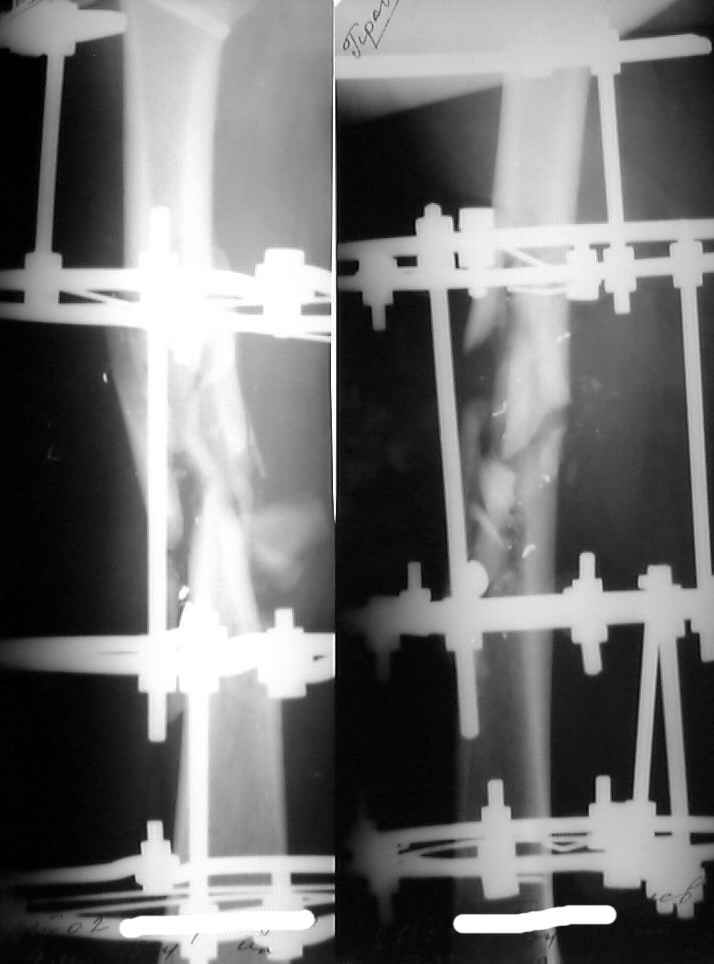

Our modest exchange experience was more optimistic so i proceed with the nailing (UFN 11 mm) before i read answers :-(

So 5th day i am about a nervous breakdown. After the surgery except the cold shower from the group a laboratory report was received that he is also HIV and hep. C infected. So i keep fingers crossed. I attached xrays and current view of the leg. All looks calm at the moment... How long to proceed with antibiotics and heparin?

The patient feels fine, no fever, ambulates with crutches, knee ROM is 0/90, and he is going to leave for home tomorrow.